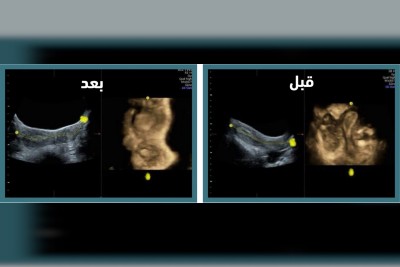

”رحم وحيد القرن“.. جراحة تُنهي معاناة فتاة من تشوه نادر

أنهت مدينة الملك سعود الطبية، عضو تجمع الرياض الصحي الأول، معاناة فتاة في الثلاثين من عمرها من تشوه رحمي خلقي نادر يُعرف بـ ”رحم وحيد القرن مصحوب بقرن بدائي“. وأوضحت المدينة أن هذه الحالة النادرة تحدث نتيجة خلل في عملية تكوين الرحم أثناء مرحلة نمو الجنين، وقد كانت المريضة تعاني من آلام حادة أثناء الدورة الشهرية، مما استدعى مراجعتها المتكررة لقسم الطوارئ لتلقي المسكنات الوريدية كل شهر. وبعد إجراء الفحوصات الطبية اللازمة،... |